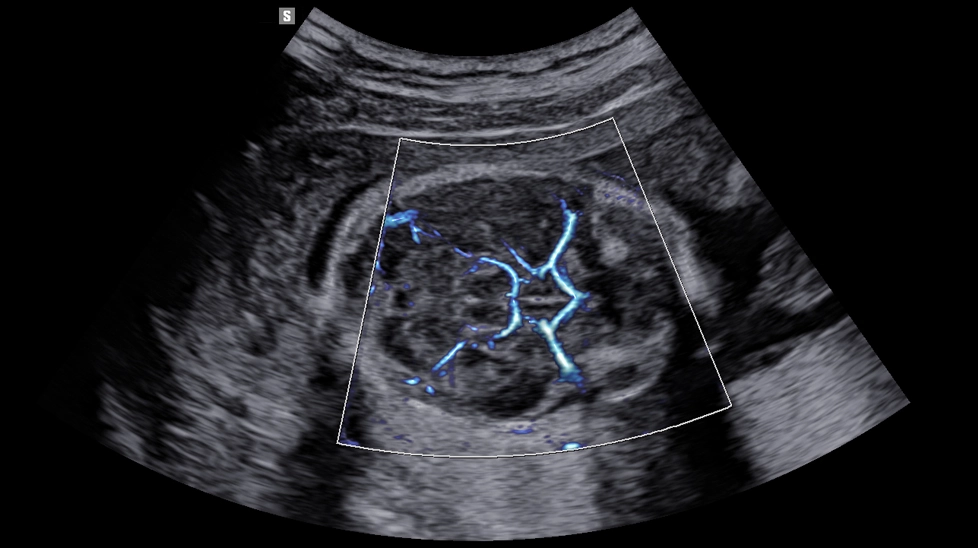

- MV Flow - технология визуализации кровотока в микроциркуляторном русле. Позволяет получить информацию о низкоскоростном кровотоке в капиллярном русле без использования контраста.

- MV-Flow - предлагает новую альтернативу энергетическому доплеру для визуализации медленного потока в микрососудистых структурах. Высокая частота кадров и расширенная фильтрация позволяют MV-Flow ™ обеспечивать детальное изображение кровотока по отношению к окружающим тканям или патологическим структурам с улучшенным пространственным разрешением.

- LumiFlow - это стереоскопическая визуализация кровотока, которая помогает интуитивно понять структуру кровотока и мелких сосудов.

MV-Flow c Lumoflow (мозг плода)

MV-Flow с Lumoflow (Брюшная полость плода)